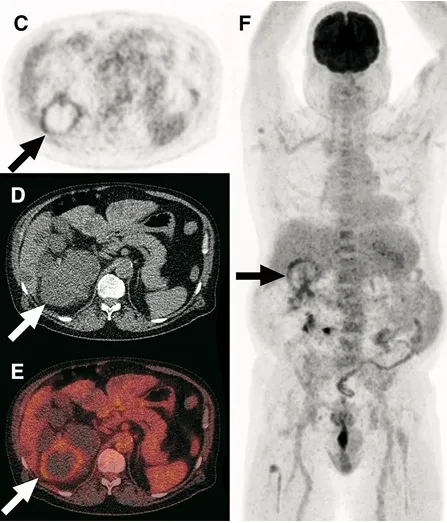

Injúria Renal Aguda (revisão Lancet 2025)